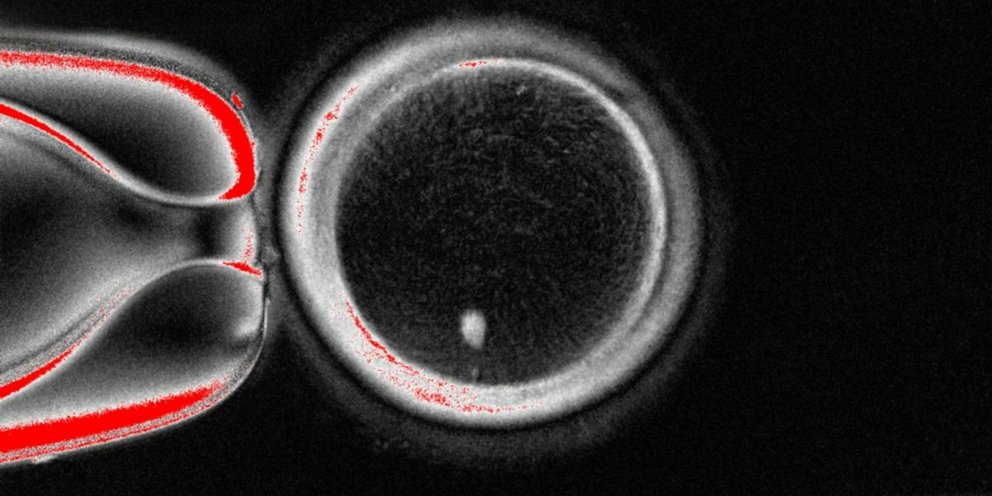

Φωτογραφία: Oregon Health & Science University

Η ομάδα του Όρεγκον ακολούθησε μια προσέγγιση παρόμοια με εκείνη που οδήγησε στη γέννηση της Ντόλυ το 1996, συλλέγοντας δερματικά κύτταρα από γυναίκες και αφαιρώντας τον πυρήνα από το καθένα. Ο πυρήνας περιέχει τα 46 χρωμοσώματα που φέρουν τα περίπου 20.000 γονίδια τα οποία συγκροτούν τον ανθρώπινο γενετικό κώδικα. Κάθε πυρήνας από κύτταρο δέρματος τοποθετήθηκε σε ένα υγιές ωάριο δότριας, από το οποίο είχε αφαιρεθεί ο δικός του πυρήνας.